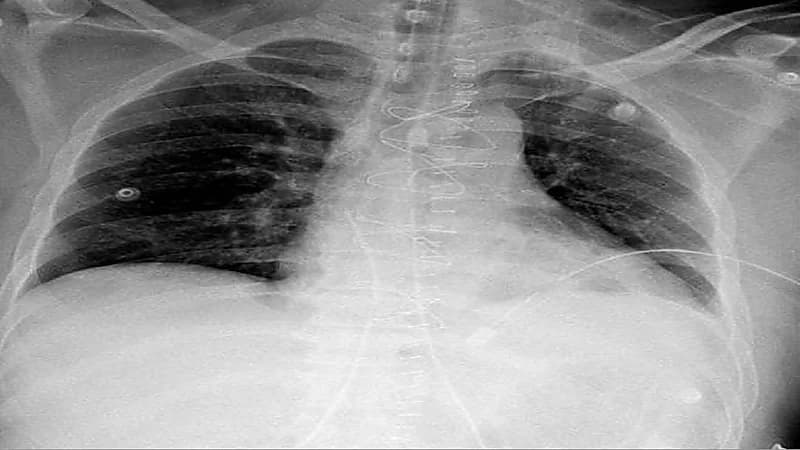

تمكن فريق طبي من مدينة الملك سعود الطبية عضو تجمع الرياض الصحي الأول من إنقاذ حياة مقيم تعرض للإصابة في منطقة الصدر.

حيث تم نقله بشكلٍ عاجل لطوارئ المدينة الطبية؛ كانت حالته خلالها غير مستقرة مع هبوط في الدورة الدموية واختلال للوعي مع وجود انتفاخ في الأوردة الوداجية، بضغط يصل إلى 60/43.

وأكدت الأشعة الصوتية وجود تجمع دموي حول القلب في تجويف التامور مع وجود استرواح هوائي حول الرئة اليسرى، ليتم نقله مباشرة إلى غرفة العمليات بواسطة الفريق الطبي المكون من استشاري الإصابات د. زيسس تولوميس، وزميل جراحة الإصابات د. أحمد فلاته، وأخصائي الجراحة العامة د. أسرار الوادعي، ويترأسها استشاري ورئيس مركز الإصابات د. شرف الدين شودري.

تم فتح صدر المريض من خلال عظمة القص، وتحرير القلب من الضغط المتكون من تجمع الدم في تجويف التامور، بعد ذلك تم التحكم بالنزيف وإصلاح عضلة القلب، وبتوفيق الله تحسن المريض وغادر العناية المركزة بعد يومين وهو بصحة جيدة.

يشار إلى أن الإصابات النافذة للقلب تعتبر نادرة جدًا وتؤدي إلى الوفاة بنسبة عالية –لا قدر الله-، حيث تتطلب إلى مركز إصابات متخصص للتعامل مع هذه الحالات في وقت قياسي.